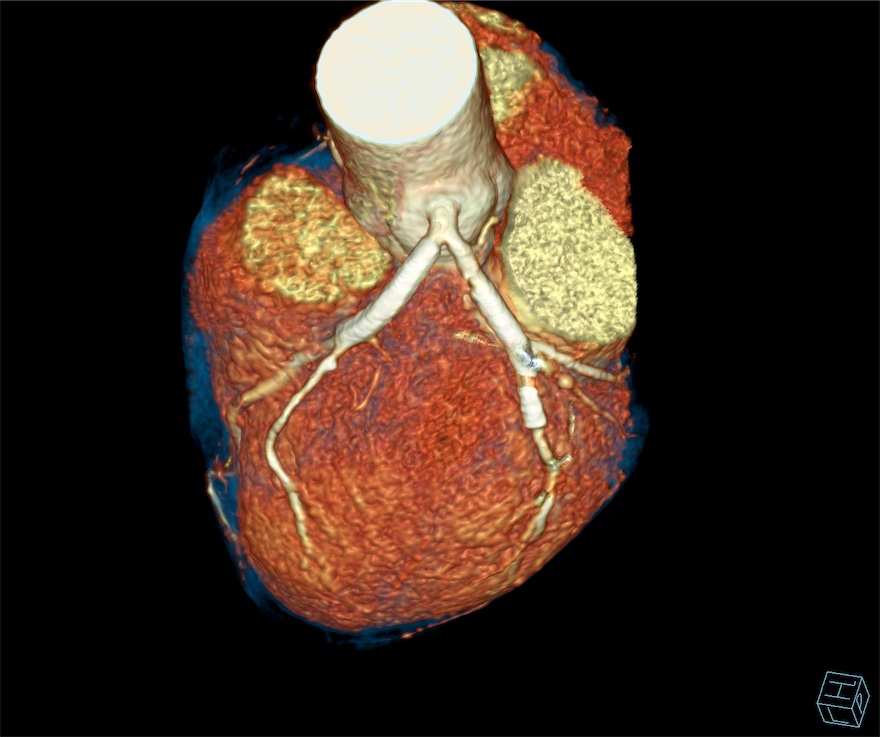

Case Study (Stent - LAD & LCX)